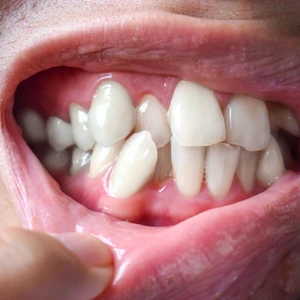

Bruxism (Teeth Grinding)

Involuntary grinding or clenching of teeth, especially during sleep, causing enamel erosion, jaw muscle fatigue, and tooth sensitivity.

Can bruxism (teeth grinding) cause TMJ disorder?

Yes. Bruxism (grinding or clenching teeth) is both a cause and a consequence of TMD. Habitual grinding places enormous stress on the TMJ, articular disc, and masticatory muscles, often leading to or worsening jaw disorders. FMS Dental treats bruxism with custom night guards, TENS therapy, and neuromuscular rehabilitation.